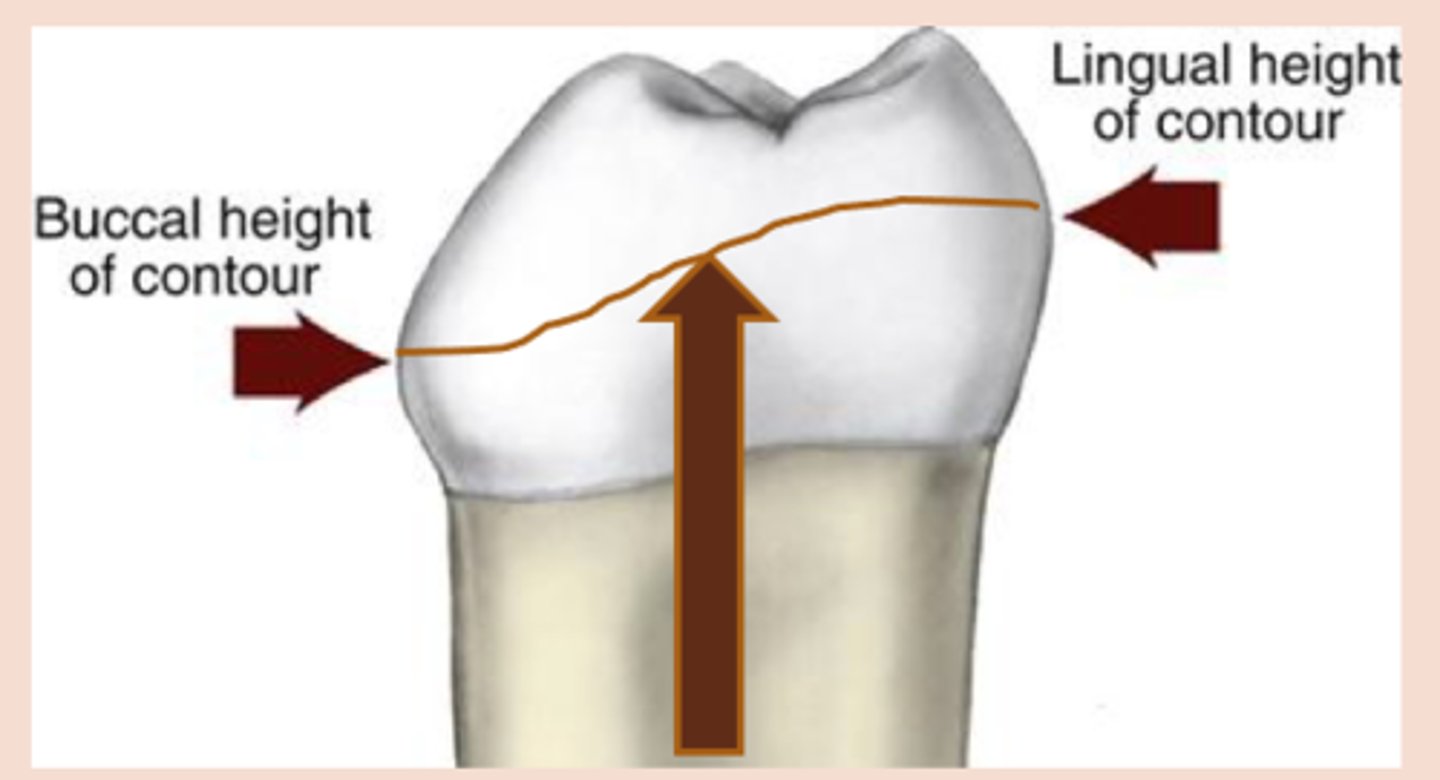

survey line

height of contour marked around the tooth

(The clasp engages a portion of the tooth surface and either enters an undercut for retention or remains entirely above the height of contour to act as a reciprocating or bracing element)

1) Retention: resistance to _______ force. Retentive arm (A) – only terminal 1/3 should be below survey line (height of

Bracing arm (B) – located entirely above the survey line